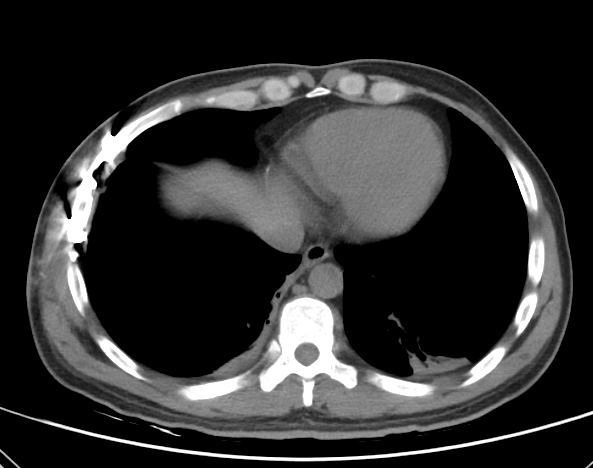

双肺挫裂伤并右侧血气胸

肋骨多发骨折是比较严重的一种肋骨骨折,它是指两根及以上的肋骨骨折,同时伴发有肋骨自身的多段骨折。该患者肋骨骨折压迫、刺破了肺部,并出现了气胸和血胸,需要进行手术治疗复位骨折,修补挫伤肺组织,胸腔闭式引流将积气、积液外引。如不及时处理,将不能够保证胸部的正常呼吸,就会造成严重的呼吸障碍,最终呼吸衰竭危及生命。

肋骨骨折: